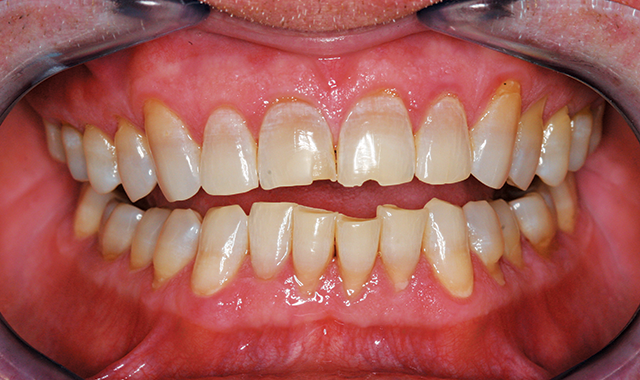

A middle-aged patient presented with a desire for a healthier, more youthful smile that was compromised by crowding and wear. A conservative approach of ABB (alignment, bleaching and bonding) was recommended, starting with aligner care with Invisalign (Fig. 1).

Fig. 1 Fig. 2

Post-orthodontic care wasn’t rushed to establish solid tooth positions and occlusion. This involves three months of retention along with deprogramming, whitening and equilibration at the end. (Fig. 2).